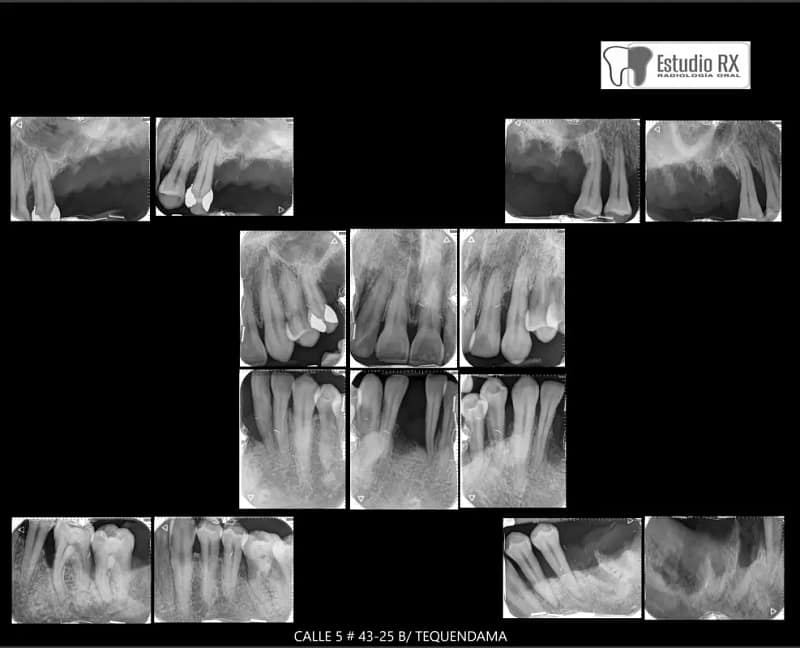

Por otro lado, la Radiografía Periapical Completa Análoga ofrece una visión integral de toda la boca, capturando imágenes detalladas de todas las áreas dentales y óseas. Este enfoque es esencial cuando se requiere un análisis exhaustivo de la salud bucal, cubriendo todos los dientes y sus estructuras de soporte.

En Estudio Rx, utilizamos tecnología análoga de alta calidad para asegurar imágenes nítidas y precisas, imprescindibles para un diagnóstico adecuado. Nuestro equipo de profesionales está dedicado a ofrecerte una atención personalizada y eficiente, garantizando que cada radiografía se tome con la máxima precisión y comodidad.